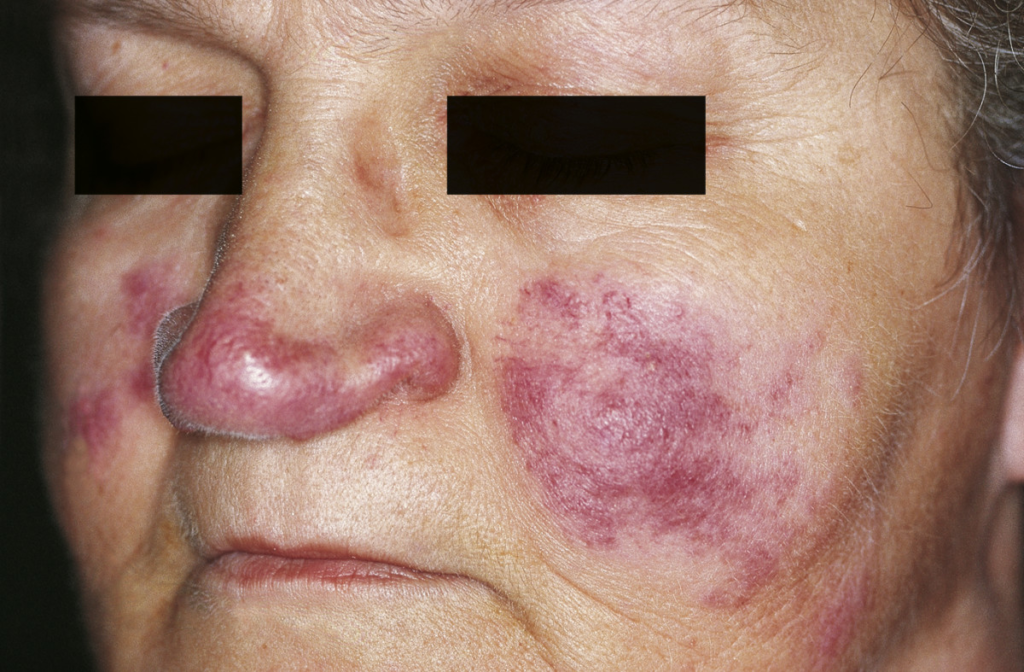

3. Lupus Pernio

- Chronic, bluish-purple discoloration

- Commonly affects the nose, cheeks, lips, and ears

- Associated with more severe or long-standing disease

- Can cause facial disfigurement if untreated